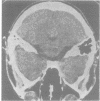

A patient with pontocerebellitis associated with infectious mononucleosis is described. The clinical picture with transitory limb and truncal ataxia was compatible with previous reports of cerebellitis. CT showed wide pontocerebellar cisterns and a hypodense area in the pons.